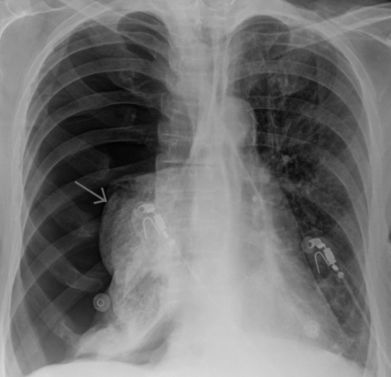

- рентгенографии грудной клетки;

- компьютерной томографии;

- исследования газового состава крови;

- ЭКГ.